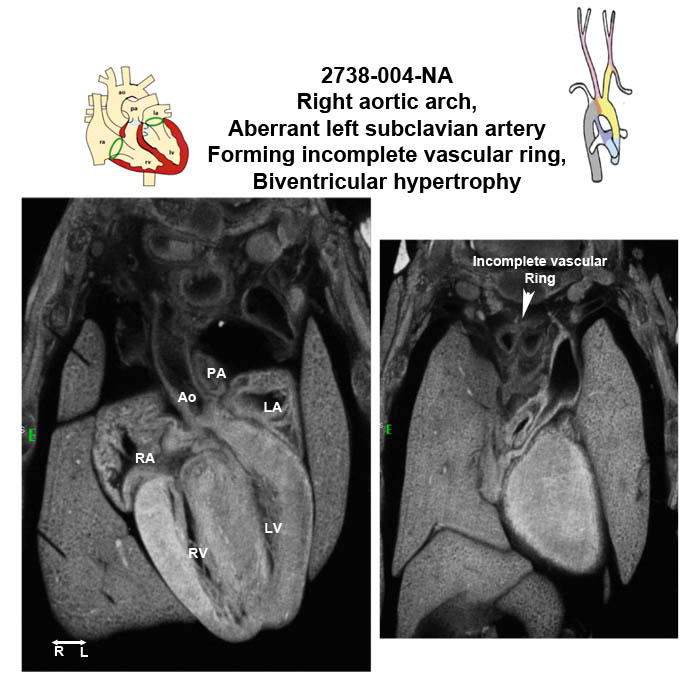

Caption EFIC Summary

b2b2738Clo Mutant line 2738; Bench to Bassinet Program (B2B/CVDC), mutation 2738 Cecilia Lo

b2b2738Clo/b2b2738Clo C57BL/6J-b2b2738Clo